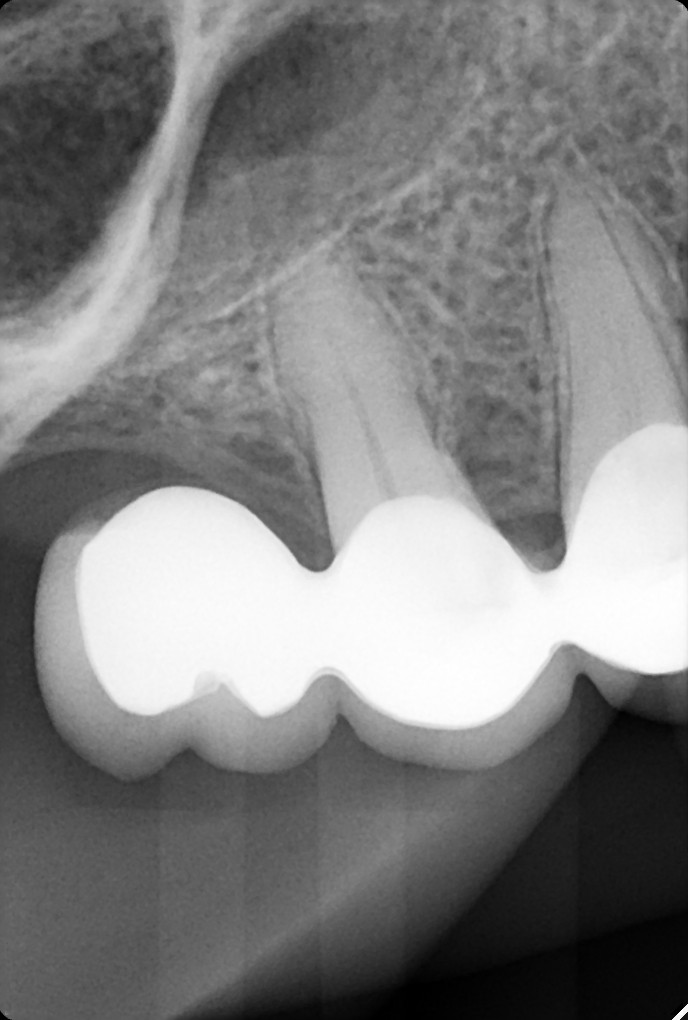

13. What option can be selected for the restoration on the lower jaw?

23. What option can be selected for the restoration on lower jaw?

29. What option can be selected for the crown over the tooth # 3.6?